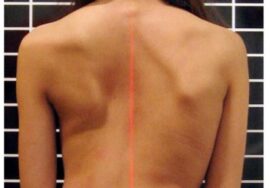

يعاني كثير من المراهقين من اعوجاج العمود الفقري المراهقي مجهول السبب (Adolescent Idiopathic Scoliosis – AIS)، وهو انحناء غير طبيعي للعمود الفقري غالبًا على شكل حرف C أو S. هذا الانحناء قد يؤثر على شكل الجسم ووضعية المراهق ويزيد القلق لدى الأهل حول صحة أبنائهم.

تقليل دوران الجذع (ATR): يقل التواء الجسم، ما يحسن مظهر الظهر عند النظر من الخلف.

إذا لاحظتِ علامات انحناء في ظهر طفلك، أو لاحظتِ عدم تماثل بين الجانبين، فلا تتردد الأن في استشارة مجانيه من طبيب متخصص.

إذا لاحظتِ علامات انحناء في ظهر طفلك، أو لاحظتِ عدم تماثل بين الجانبين، فلا تتردد الأن في استشارة مجانيه من طبيب متخصص.

إذا لاحظتِ علامات انحناء في ظهر طفلك، أو لاحظتِ عدم تماثل بين الجانبين، فلا تتردد الأن في استشارة مجانيه من طبيب متخصص.